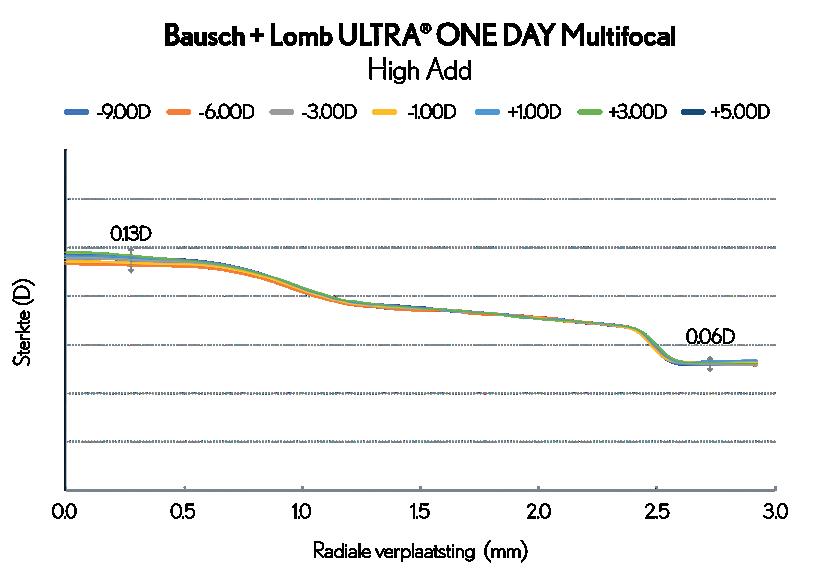

3-ZONE PROGRESSIVE™ DESIGN LEVERT CONSISTENT STERKTEPROFIEL OVER VOLLEDIGE BEREIK VAN BESCHIKBARE PARAMETERS3

Het 3-Zone Progressive™ Design zorgt voor moeiteloze helderheid en naadloze overgangen van nabij tot veraf, om stress en vermoeidheid van de ogen te helpen verminderen1. Bausch + Lomb ULTRA® ONE DAY Multifocal contactlenzen vertonen minder variatie in sterkte over het gehele leverbereik van de lens, wat betekent dat de visuele ervaring voor de patiënt consistenter is, ongeacht de specifieke voorgeschreven sterkte.

Een stabiel en voorspelbaar lensontwerp is van cruciaal belang om de ‘drop-out’ van contactlensdragers te verminderen, die vaak wordt veroorzaakt door een combinatie van slecht zicht en ongemak door droogte.